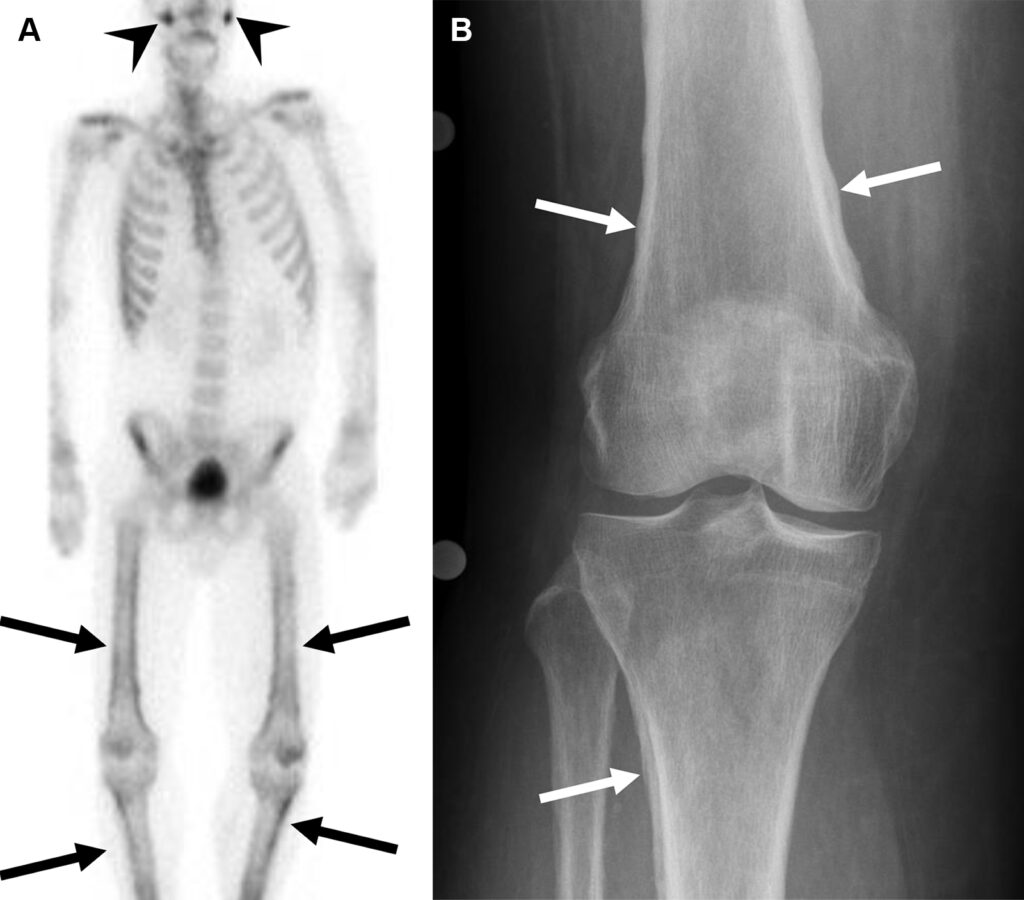

Malattia di Erdheim-Chester in un uomo di 47 anni con dolore osseo aspecifico.

La scintigrafia ossea whole-body evidenzia un’intensa ipercaptazione simmetrica e confluente a carico delle ossa lunghe (in particolare distretto dia-metafisario ed epifisario di ginocchia e caviglie). Come reperto incidentale, si osserva un ristagno di tracciante nel rene destro, indice di ostruzione delle vie urinarie.

La TC conferma una marcata osteosclerosi nelle medesime sedi ipercaptanti e la presenza di una massa tissutale infiltrante che avvolge simmetricamente i reni (aspetto a “cercine” o hairy kidney) e infiltra il mesentere. Questa fibrosi retroperitoneale spiega l’ostruzione dell’efflusso renale destro rilevata in scintigrafia.

La malattia di Erdheim-Chester è una rara istiocitosi non-Langerhans caratterizzata da una proliferazione sistemica di macrofagi. Il pattern di osteosclerosi simmetrica dia-metafisaria bilaterale delle ossa lunghe, associato all’infiltrazione perirenale, è considerato un quadro radiologico quasi patognomonico per questa patologia.